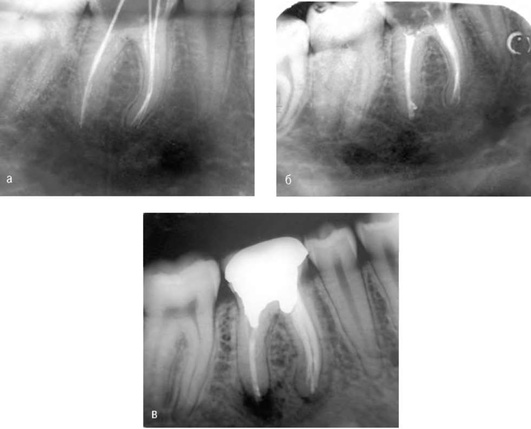

Учитывая, что клиническая картина хронического периодонтита может отсутствовать или быть незначительно выраженной для дифференциальной диагностики обязательно проведение рентгенографии. На рентгенограмме определяют деформацию периодонтальной щели с нарушением четких контуров компактной пластинки кости альвеолы. Многие случаи хронического апикального периодонтита связаны с некачественным эндодонтическим лечением (рис. 13-7).

image

Рис. 13-7. Хронический апикальный периодонтит зуба 35

Однако чаще на рентгенограмме у верхушки корня обычно определяют ограниченный очаг разрежения костной ткани округлой или овальной формы с четкими границами и остеосклерозом (рис. 13-8).

Рис. 13-8. Внутриротовая рентгенограмма. Деструкция костной ткани с четкими контурами у верхушек корней зубов 46 (а), 22 (б)